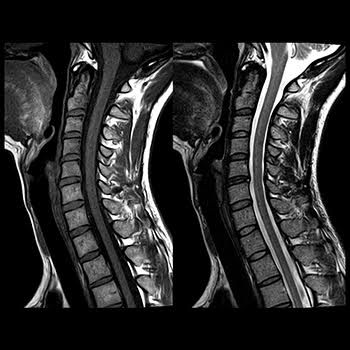

Our High-field MRI captures high-quality images. Our technicians who operate the scanner are certified in MRI and will stay in constant communication with you throughout your scan.

An MRI of the soft-tissue structures of the body—such as the heart, liver and many other organs - are more likely in some instances to identify and accurately characterize diseases than other imaging methods. This detail makes MRI an invaluable tool in early diagnosis and evaluation of many focal lesions and tumors.

MRI uses a powerful magnetic field, radio frequency pulses and a computer to produce detailed pictures of organs, soft tissues, bone and virtually all other internal body structures. The images can then be examined on a computer monitor, transmitted electronically, printed or copied to a CD. MRI does not use ionizing radiation (x-rays).

Detailed MR images allow physicians to evaluate various parts of the body and determine the presence of certain diseases. - How should I prepare for the procedure?